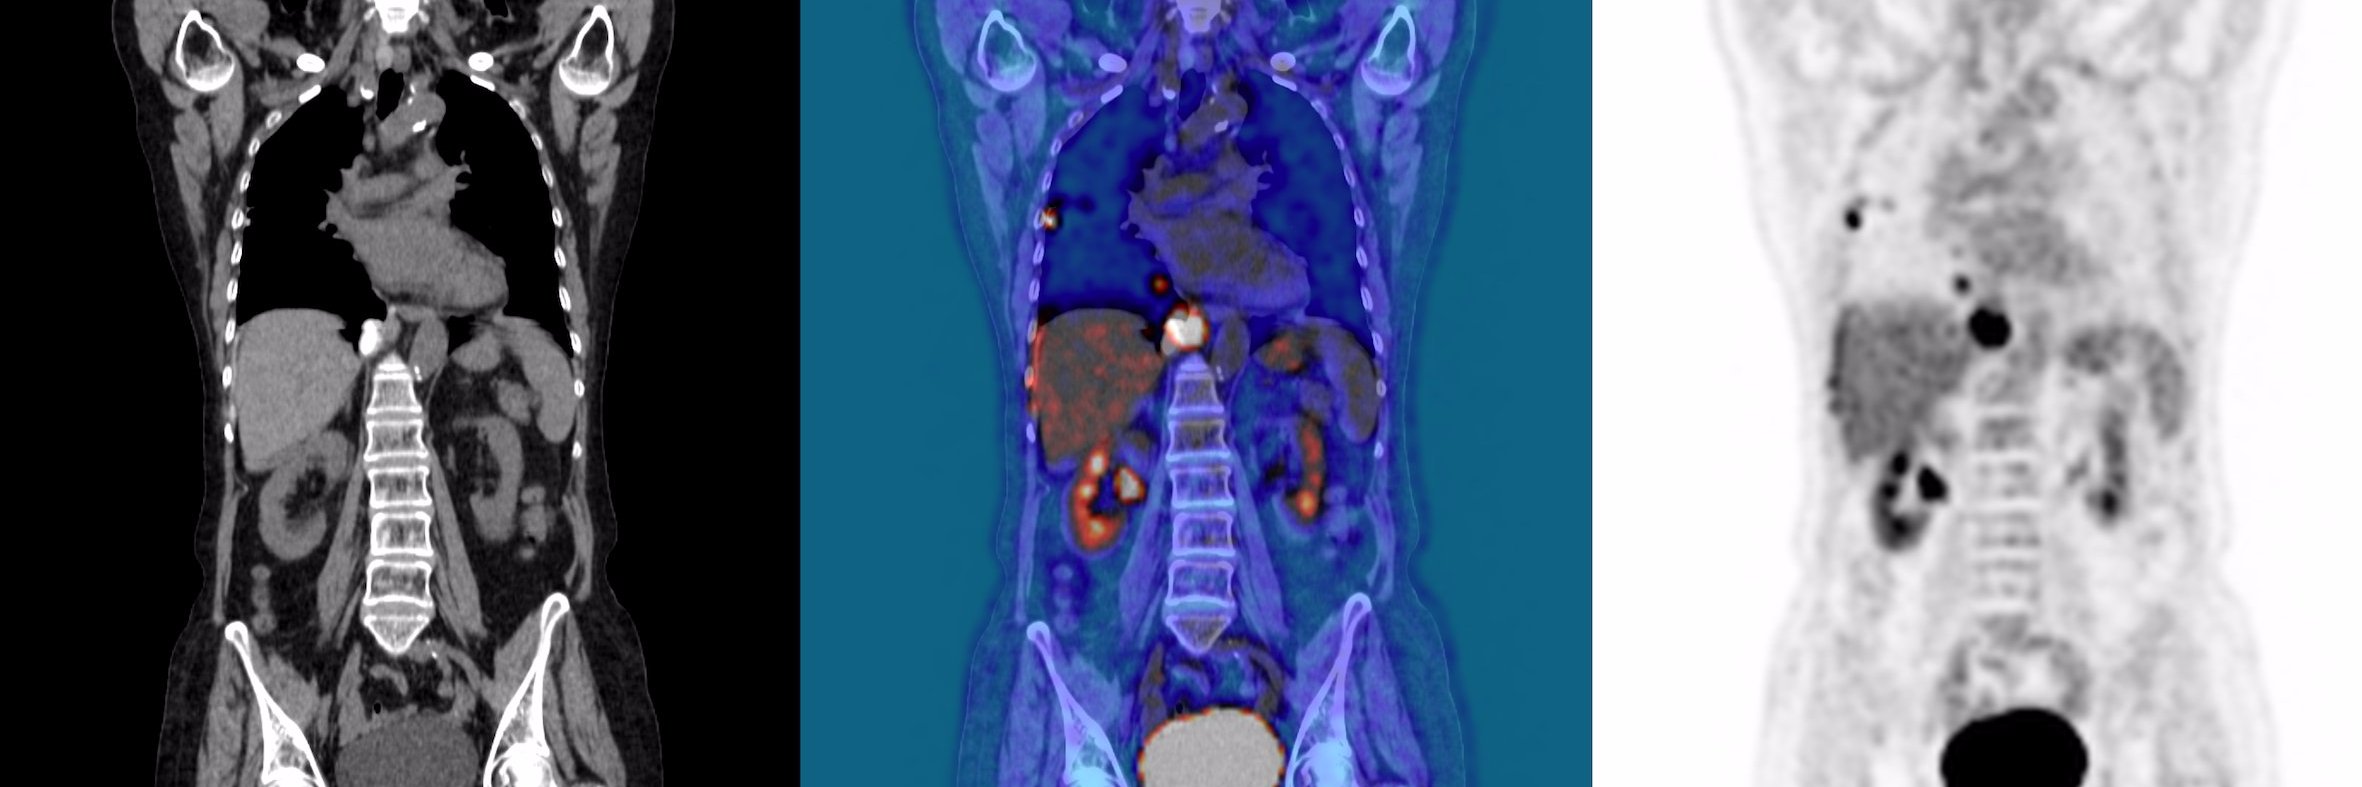

Just published: Leveraging #MachineLearning to predict #ProstateCancer hypoxia using prostate #MRI #Radiogenomics link.springer.com/article/10.100… Great #multidisciplinary #teamscience @LeedsCancerRes @MCRCnews @AcademyRad @LeedsRadiology @LeedsMedHealth @LTHTResearch @CRUKresearch